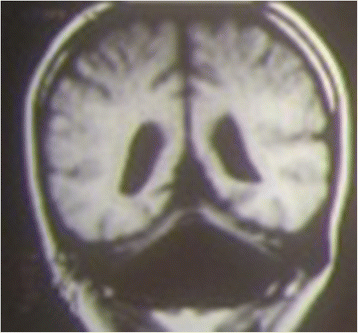

Background: Ataxia is a sign of different disorders involving any level of the nervous system and consisting of impaired coordination of movement and balance. It is mainly caused by dysfunction of the complex circuitry connecting the basal ganglia, cerebellum and cerebral cortex. A careful history, physical examination and some characteristic maneuvers are useful for the diagnosis of ataxia. Some of the causes of ataxia point toward a benign course, but some cases of ataxia can be severe and particularly frightening.

Methods: Here, we describe the primary clinical ways of detecting ataxia, a sign not easily recognizable in children. We also report on the main disorders that cause ataxia in children.

Results: The causal events are distinguished and reported according to the course of the disorder: acute, intermittent, chronic-non-progressive and chronic-progressive.